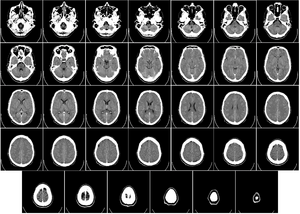

Компьютерная томография головы

Компьютерная томография (КТ) или компьютерная аксиальная томография (КАТ) использует серии рентгеновских лучей, направленных на голову, с большого количества разных направлений. Обычно её используют для быстрой визуализации ЧМТ. При КТ используют компьютерную программу, что осуществляет цифровые интегральные вычисления (инверсию преобразования Радона) измеряемой серии рентгеновских лучей. Она вычисляет, насколько эти лучи абсорбируются объёмом головного мозга. Обычно информация представлена в виде срезов мозга[4].